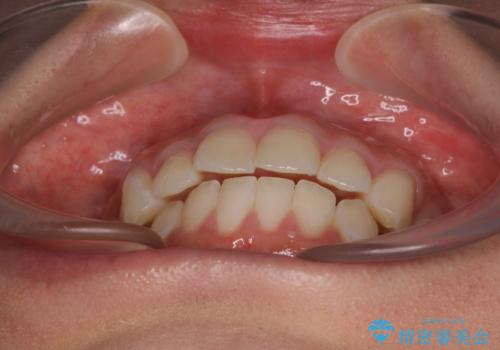

- 口元の突出感と奥歯のむし歯を気にして来院された患者様です。

通常は上下左右の第一小臼歯4本を抜歯することになりますが、左側下顎の第二小臼歯は既に根管治療をされており、予後が良くないとのことでこの歯を抜歯し、ワイヤー装置にて矯正治療を行うこととしました。

第二小臼歯抜歯はイレギュラーな治療手段であり、治療期間が延びる傾向にありますが、予定よりも早い2年間で終えることができました。